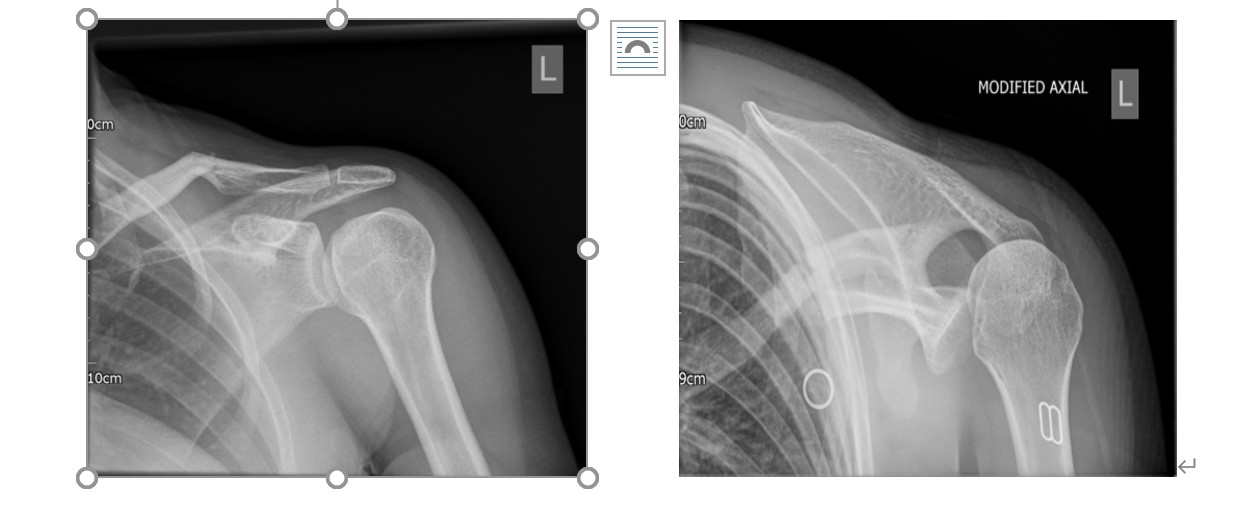

1. X线片。当正位X线片上出现肱骨头卡压在关节盂后侧盂缘上而导致的肱骨内旋、肱骨头呈圆形外观的“灯泡症”(the light bulb sign)、前盂缘和肱骨头之间的距离超6 mm的肩胛盂“空虚增宽症”(therimsign),以及肱骨头与关节盂撞击骨折所形成的垂直线影时,可高度怀疑存在PSD。腋位X线片对于PSD的诊断同样至关重要,其可以清晰地显示肱骨头位于肩胛盂后方,并能帮助评估肱骨头前内侧骨缺损的大小。如果患者肩关节不能外展,则可行肩胛骨侧位片(Y位片),PSD患者肱骨头位于“Y”位的肩峰喙突连接线后方。因此,推荐对肩关节外伤的患者常规进行肩关节正位、腋位、肩胛骨侧位片(Y位片)的X线检查,这样可以显著减低PSD的误诊率。

肱骨头向后方脱位,肱骨头前方骨缺损与肩胛盂后缘啮合